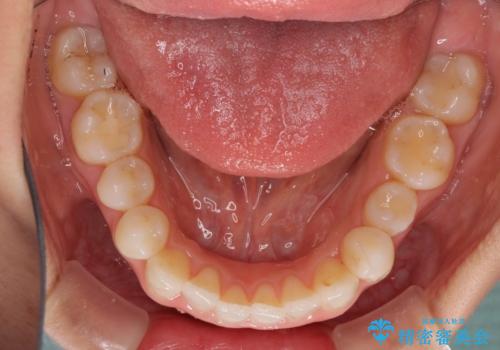

治療を長期化させたくないとのご要望があったので、左下の90度捻転した歯は、捻転した状態のゴールとしました。

反対咬合を改善したことで、歯ぎしりしたときの引っかかる感じがなくなり、奥歯への負担を大きく軽減することができました。